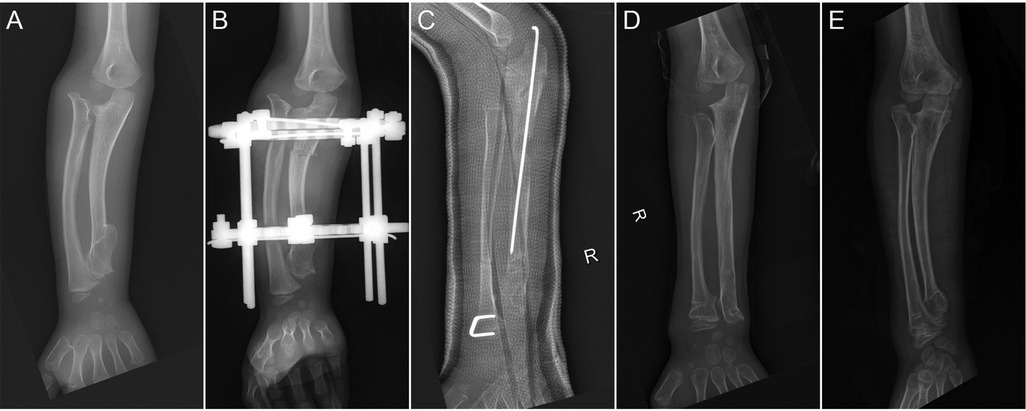

Forearm deformity was assessed on anteroposterior and lateral radiographs described by Burgess and Cates (10): radial articular angle (RAA), ulnar length percent, ulna variance (UV), radial variance (RV), and radial bow (RB) (Figure 1). The RAA is defined as the angle formed between the distal articular surface of the radius and the longitudinal axis of the forearm. The ulnar length percent was calculated by dividing ulnar length (styloid process tip to olecranon edge) by radial length (proximal-to-distal physeal centers). UV is defined as the perpendicular distance between the distal end of the ulna and the distal radial growth plate. A positive UV indicates that the ulna extends beyond the radius distally. RV represents the perpendicular distance from the radial head to the coronoid process tip. A positive RV signifies that the proximal radius projects farther than the coronoid process. The lengthening distance (LD) is the distance between the proximal and distal fragments of the ulna on the first follow-up radiograph after the final extension (Figure 1). Pre- and postoperative elbow/forearm range of motion were recorded.

Figure 1

X-rays of four forearms are displayed.\n\nPanel A: Shows measurements of radial angulation and radial bone lengths marked by red lines labeled \

Figure 1. Diagrams showing the radiological measurements. (A) The radial articular angle (RAA) and the radial bow (RB); (B) the ulna variance (UV) and the radial variance; (C) the ulnar length percent; and (D) the lengthening distance (LD).